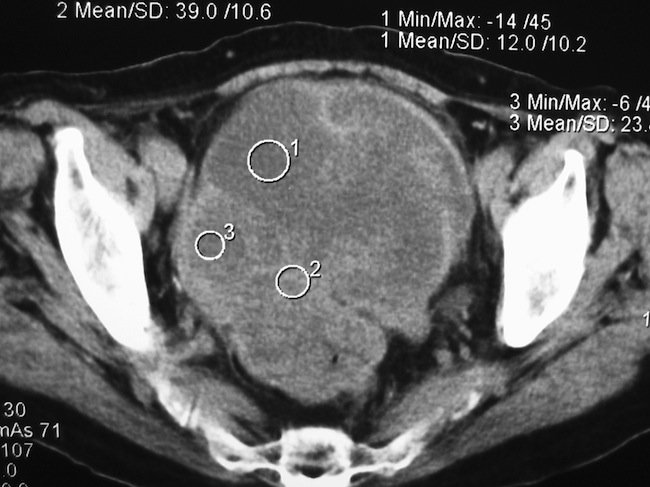

Диагностический этап включал эндоскопическое исследование толстой кишки, биопсию и гистологическую верификацию опухоли, а также выполнение компьютерной рентгеновской или магнитно-резонансной томографии малого таза и живота (рис. 1).